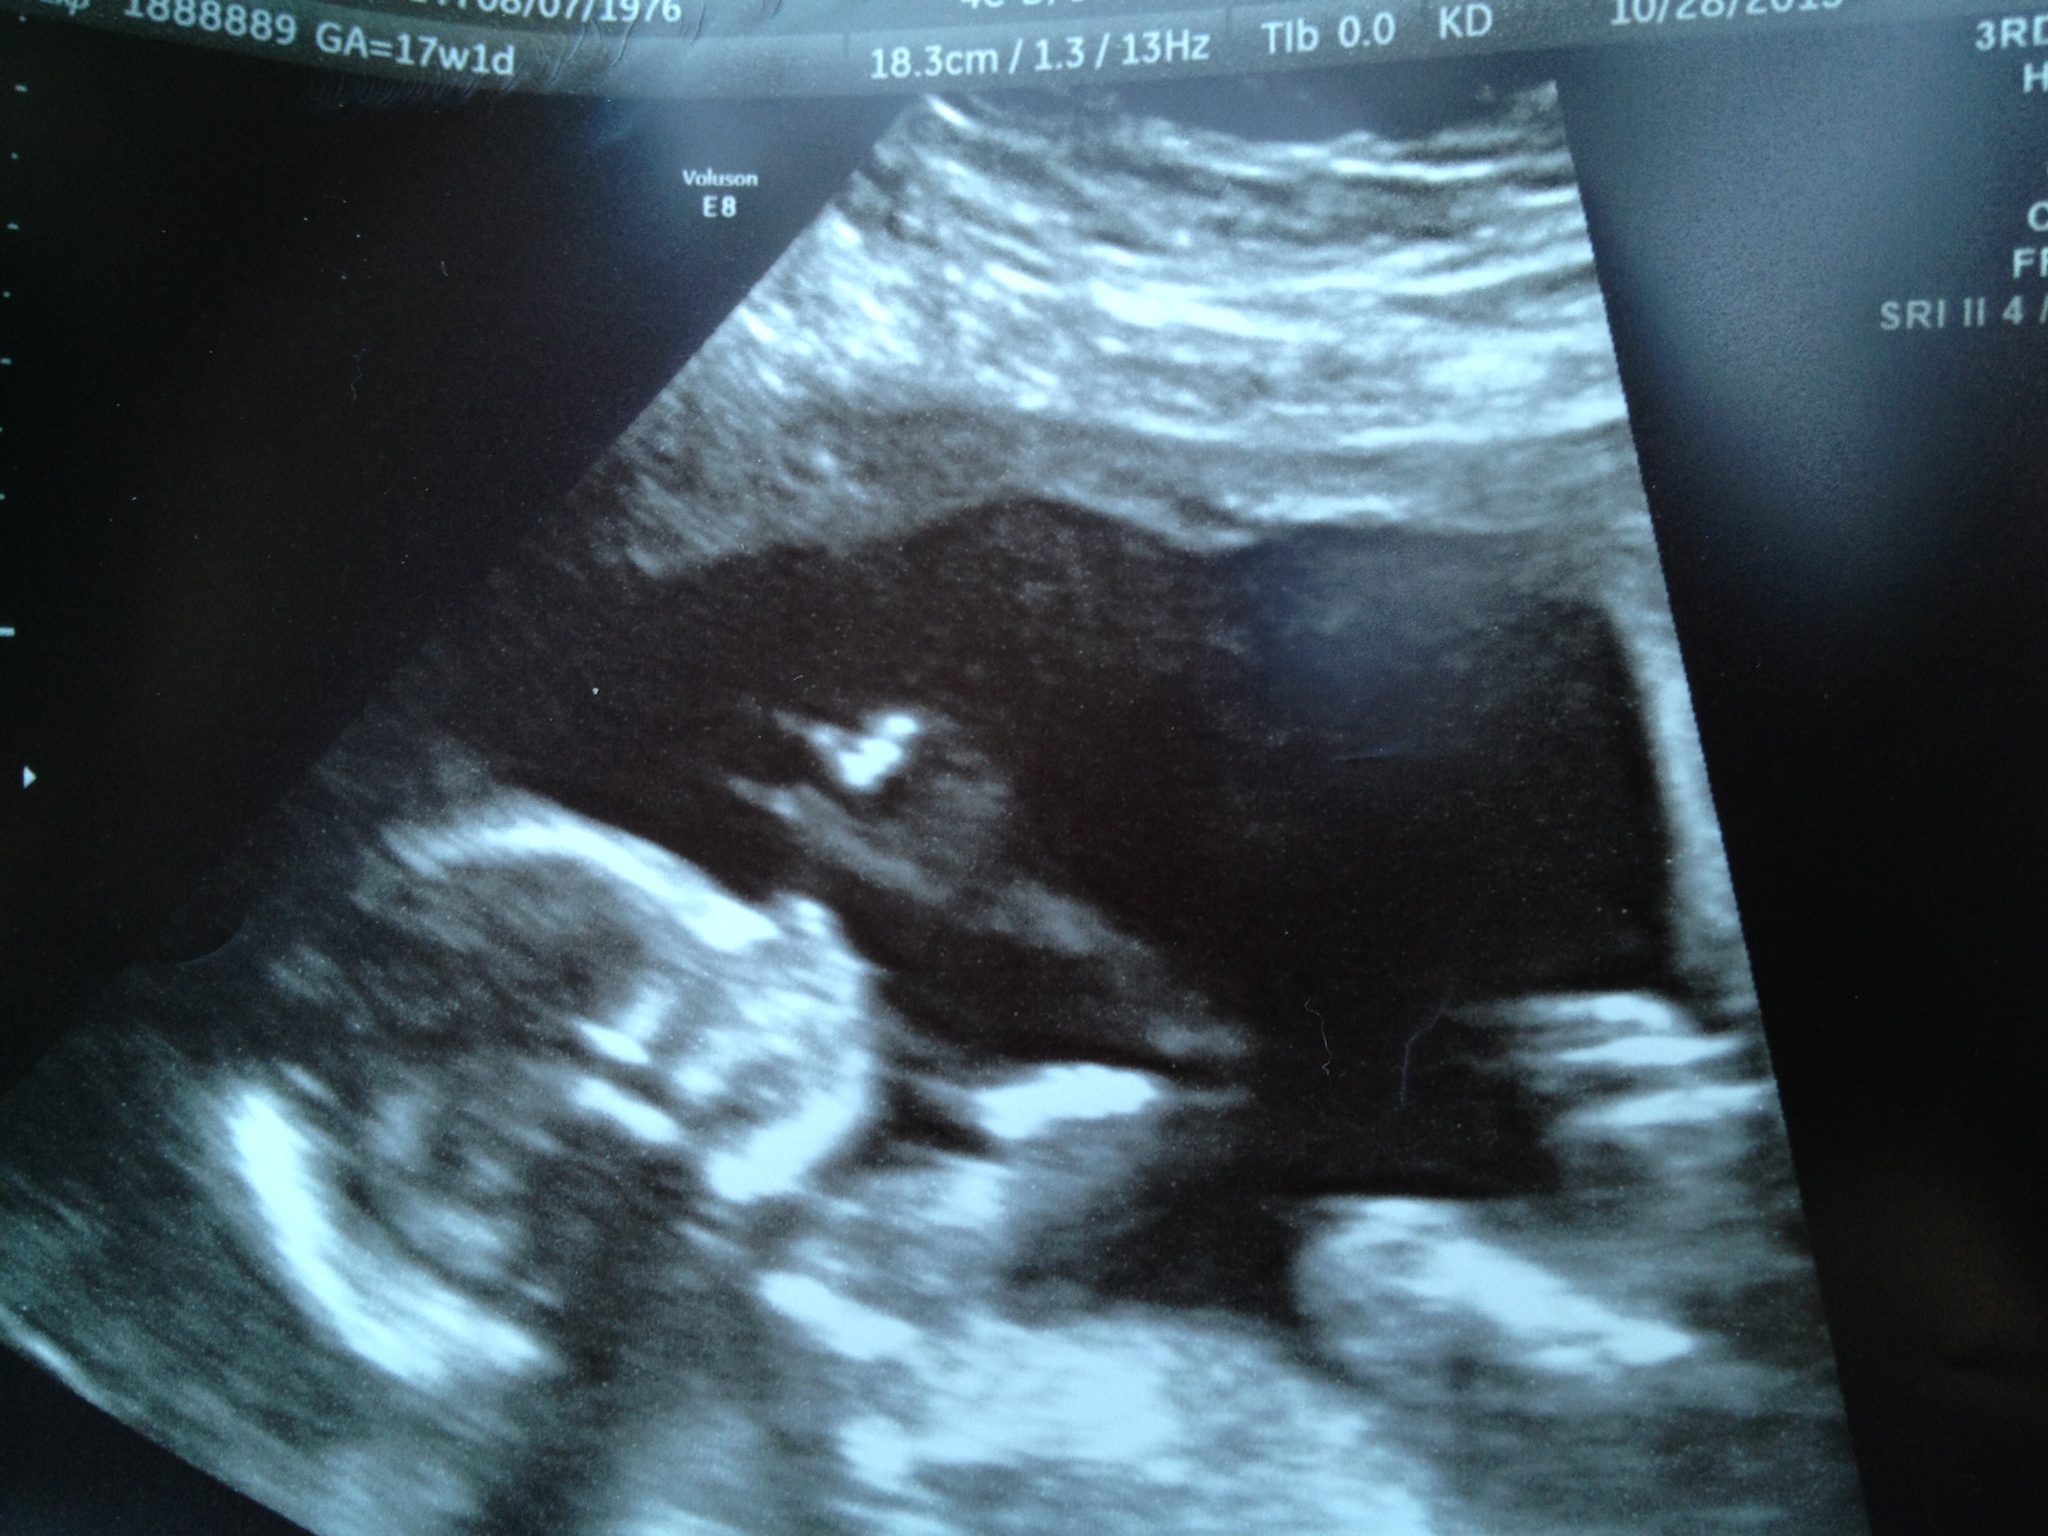

Sharon then says, “But you’re pregnant… see – there is the heartbeat.” I leaped out of my chair and said “ARE YOU FUCKING SERIOUS?” As I ran to get as close to the video monitor as I could. I didn’t believe it. I couldn’t believe it. From doom and gloom just mere minutes before, to the most amazing news one could ever receive. To be honest, I am tearing up now as I type this because that day was filled with so much raw emotion. Anne was in disbelief as she placed her face in her hands.

There have been many times in my life when I wasn’t sure what to do. This was one of them. Do I run over and hug and kiss my wife? Or do I run over and hug and kiss Sharon? As we both tried to catch our breath, Sharon left to get the doctor. Part of me still couldn’t believe what my ears were hearing. Not only was Anne pregnant, but there was a heartbeat. The doctor came in as we were still wrapping our heads around what had just happened. I can imagine the looks on our faces were similar to a 10 year old kid getting off of his first roller coaster. Because that was certainly what our emotions had been put through for a few weeks.

She too confirmed what our new best friend Sharon has told us minutes before. And based on what she could see, Anne was roughly 6 weeks pregnant. Ironic that was the same age that we had lost the previous 2 pregnancies. So with cautious optimism we left the office. I could barely contain my emotions. If there is video footage from a parking lot on YouTube of a white guy dancing a ridiculous jig… that’s likely me.